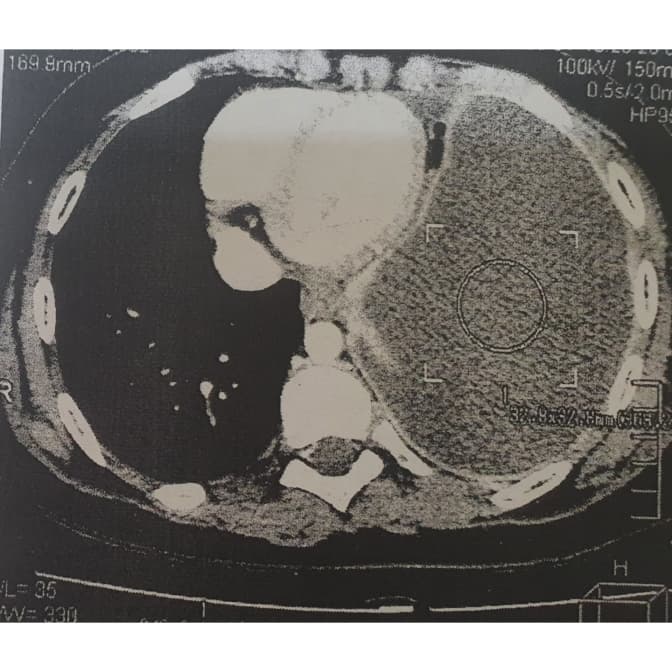

Львівські медики діагностували у Михайлика з Хмельниччини нагноєну кісту лівої легені великих розмірів із зміщенням середостіння вправо. Із такою вродженою вадою хлопчик прожив 10 років, не знаючи про це. Зі слів мами хлопчика, за життя дитині жодного разу не робили рентген, тому не могли знати про таку ваду.

Діагноз її вразив – те, що можна було діагностувати одразу після народження сина, виявили через 10 років. А за словами лікаря-хірурга Олега Леніва, кіста була настільки великою, що займала всю ліву половину грудної клітки. Із роками це спровокувало суттєве зміщення серця дитини в праву сторону.

«Ми обстежили дитину і прийняли рішення про оперативне втручання з видалення кісти. Звичайно ж, такого виду оперативні втручання є високого ступеня ризику, але тригодинна робота наших хірургів пройшла успішно, післяопераційний період також пройшов без ускладнень», – додав лікар.